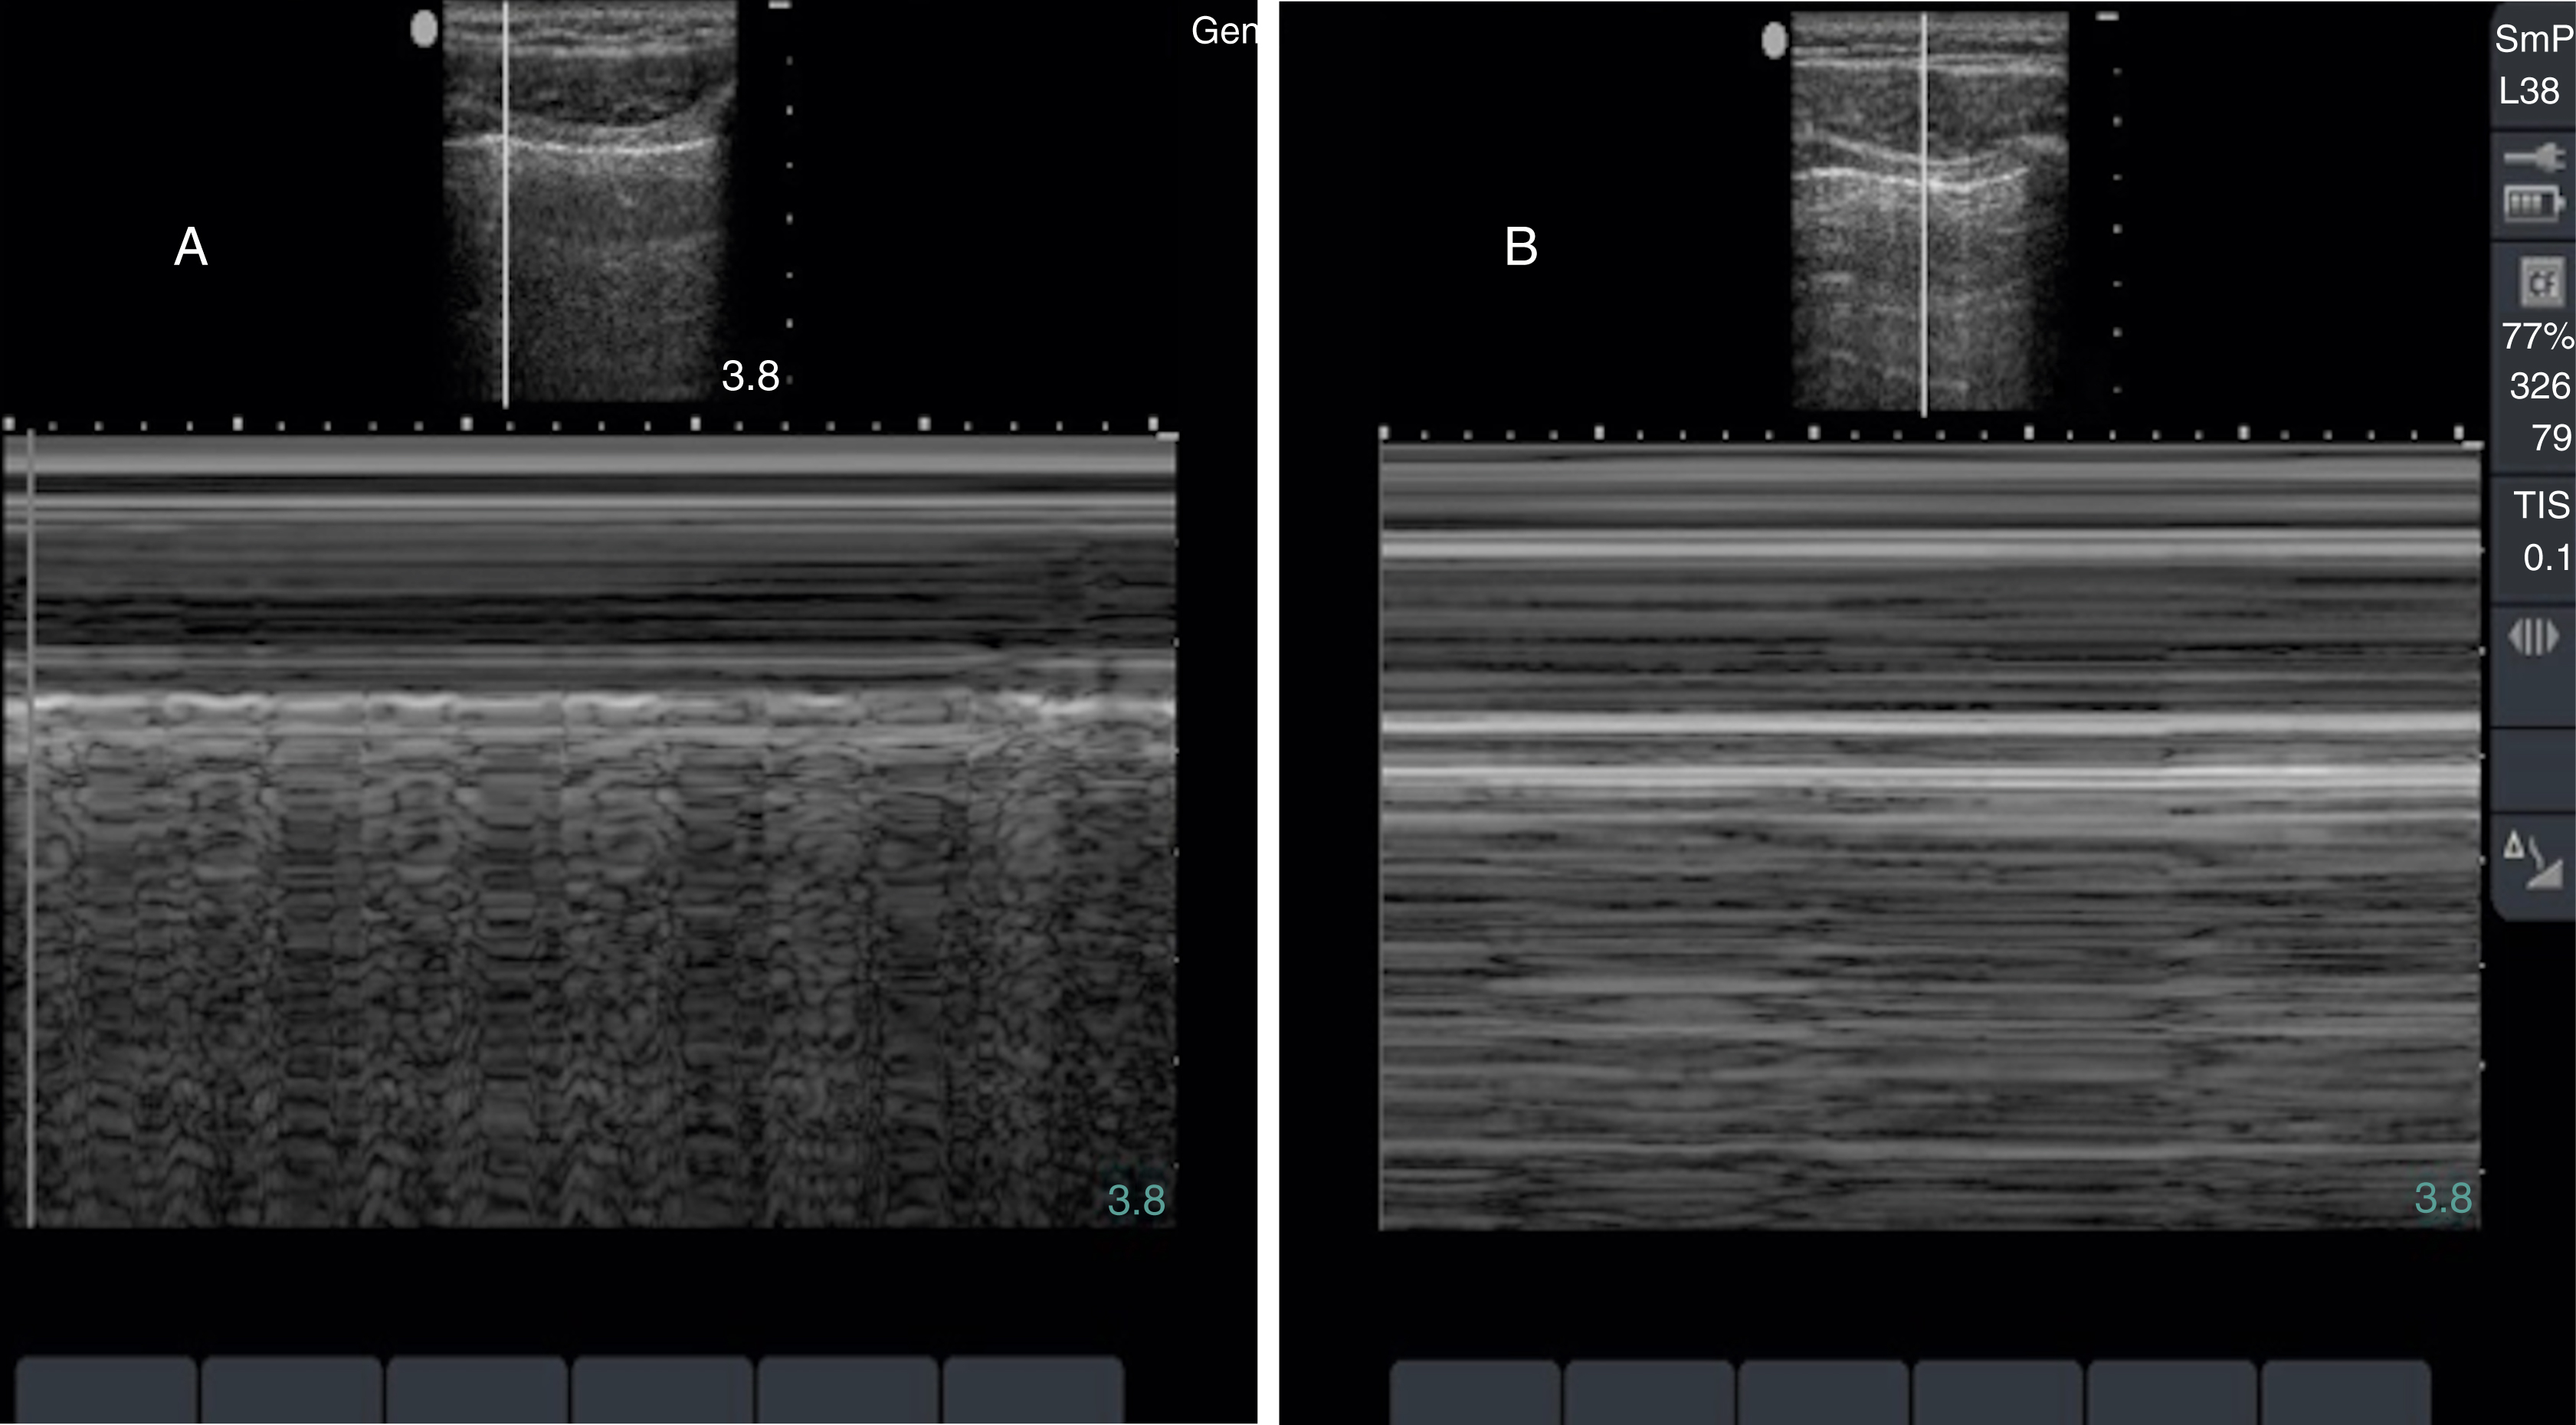

The visualization of lung sliding excludes the presence of a pneumothorax at that location on the patient’s chest wall. Although M-mode and color Doppler techniques have been described as adjuncts to the evaluation of patients with suspected pneumothorax, neither is a necessary component of the examination. Absent lung sliding can result from a variety of causes in addition to pneumothorax, including pleural adhesions or consolidations, blebs, pleurodesis, partial or complete pneumonectomy, and contralateral mainstem bronchus intubation ( Fig. e3.15 ). A lung point sign is identified at the border of the pneumothorax, where the image shows absent lung sliding until the lung moves into the interspace with respiration ( Video e3.12 ).

M mode images of the lung. (A) Normal lung with “seashore” sign. (B) Pneumothorax with “stratosphere” or “barcode” sign.